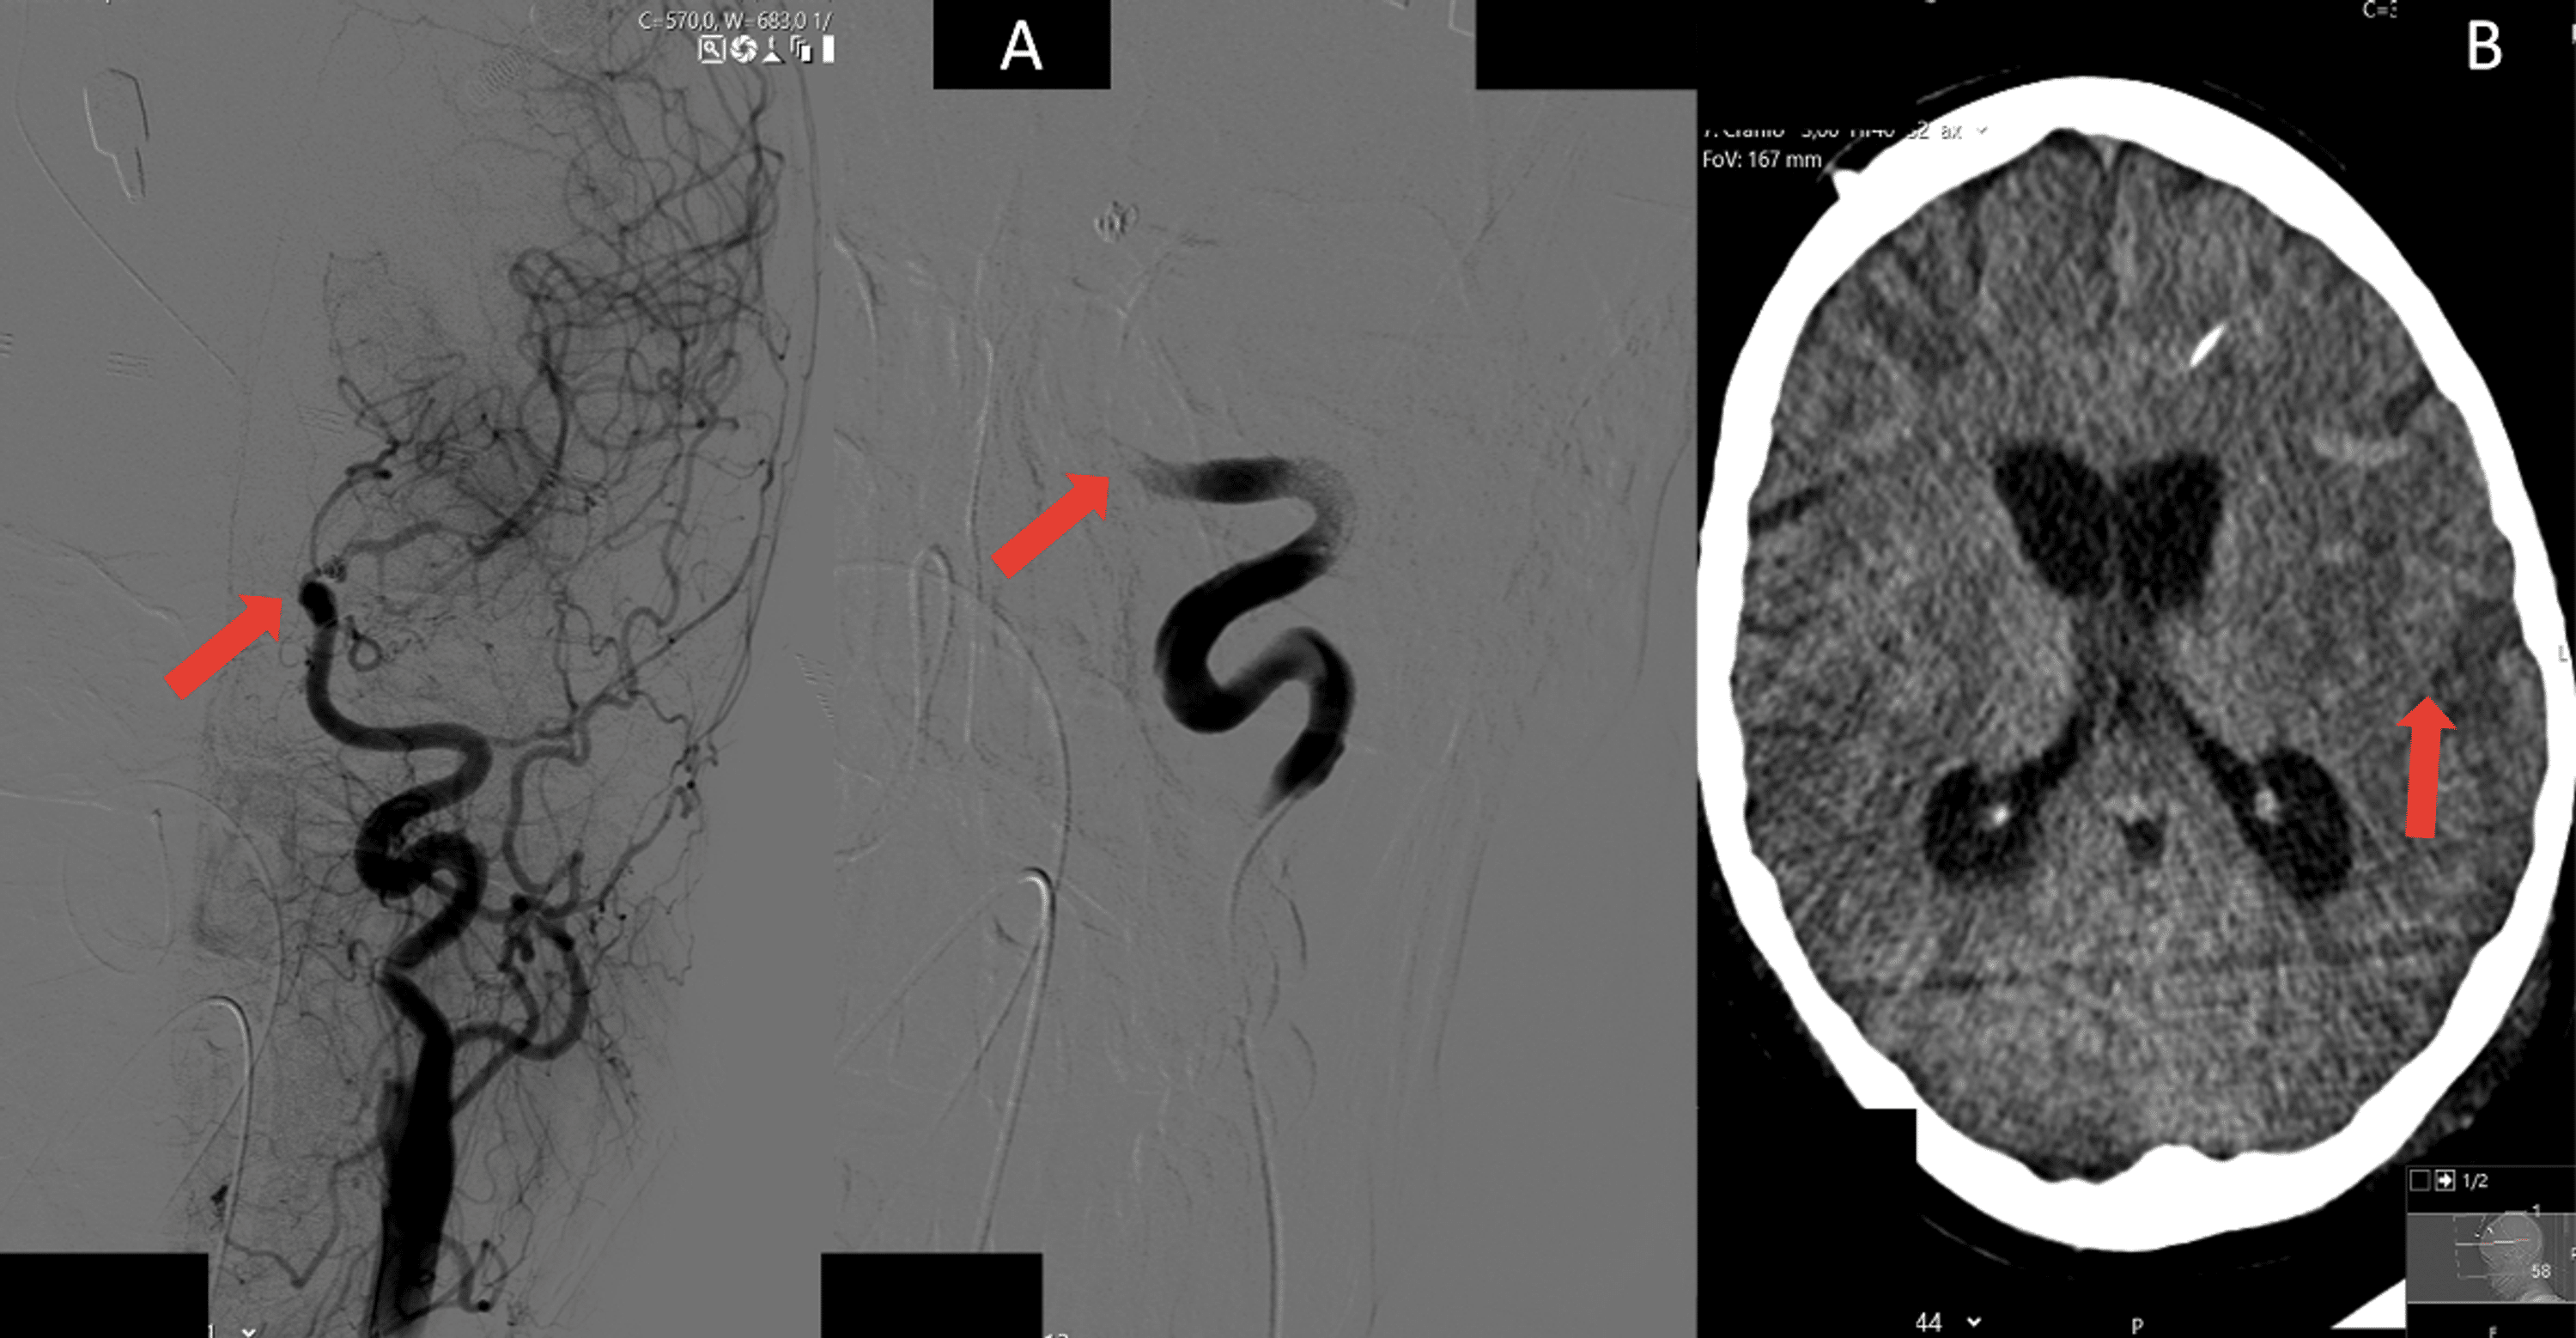

Acute right TICA occlusion at ophthalmic tract (with arrow in a and Catheter Induced Vasospasm The term coronary artery spasm (cas) refers to a sudden, intense vasoconstriction of an epicardial coronary artery that causes vessel occlusion or near occlusion. Coronary artery vasospasm (cavs) plays an important role in acute chest pain syndrome caused by transient and partial or. Catheter Induced Vasospasm.